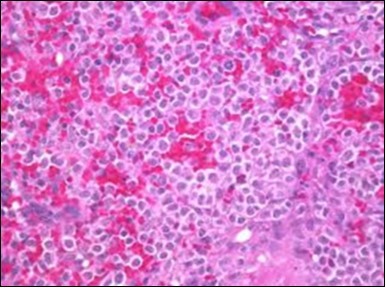

Figure 6.HCL: disseminated hairy cells with a clear cytoplasm(22).

HCL: disseminated hairy cells with a clear cytoplasm(22).